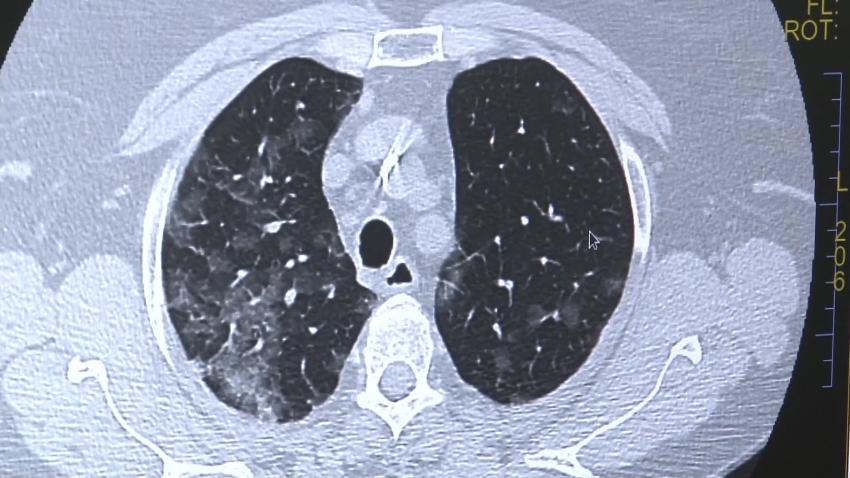

“Pacientul sau medicul acestuia pot să introducă în platformă imagini CT,istoricul medical, informații despre alte afecțiuni dar pot să adauge și probele funcționale pe care le-a făcut pacientul de-a lungul timpului, de exemplu, analiza de spirometrie. Odată finalizată această etapă, informațiile întră în atenția echipei de specialiști ai spitalului nostru care evaluează cazul. În unele situații sunt solicitate informații sau investigații suplimentare, după care echipa noastră se pronunță asupra diagnosticului, practic realizează o încadrare în boală. Opinia medicală a echipei de pneumologi și radiologi vine însoțită de recomandări de investigații și monitorizare. Nu oferim însă tratament”, spune SL. Dr Diana Manolescu, director medical Spitalul de Boli Infecțioase și Pneumoftiziologie Dr. Victor Babeș Timișoara.

“Pneumonia Interstițială Difuza( PID) reprezintă un grup de peste 200 de afecțiuni respiratorii care afectează structura anatomică a plămânului. Diagnosticarea este dificila din cauza suprapunerii numărului mare de boli care au aceleași simptome. De aceea, diferență o face experiență medicală îndeosebi în ceea ce privește partea imagistică. Din păcate, unele dintre afecțiuni sunt foarte severe si au o cu o rată de supravițuire medie de 4-5 ani”, spune SL. Dr Diana Manolescu, director medical Spitalul de Boli Infecțioase și Pneumoftiziologie Dr. Victor Babeș Timișoara.